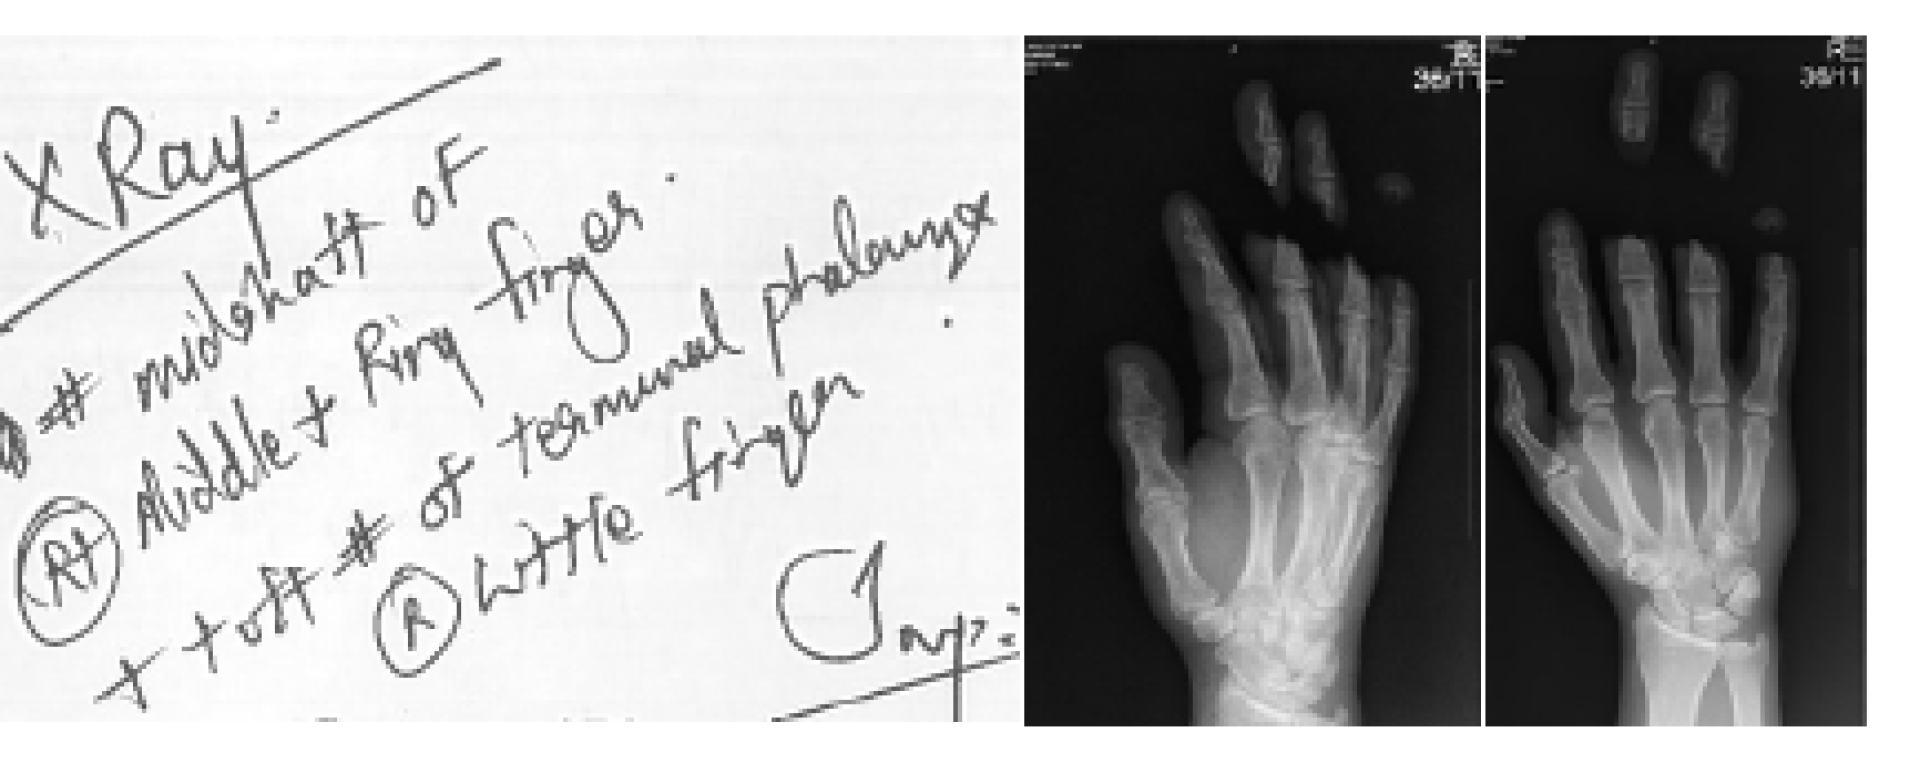

When the crumble mixture was not discharging into the discharge bin, he removed the safety key, opened the top lid, the machine stopped working and then he closed the lid and the machine started working again. Mr. Radecki did this hoping the blockage will discharge into the discharging bin again. It did not work so he removed the discharge bin and put his right hand up into the machine to try to remove the blockage. When Mr. Radecki put his right hand up the machine, suddenly and without warning, three of his fingers were severed. He started shouting and screaming to his colleagues and at the same time kept pushing the stop button on the machine, which was not stopping the machine. He does not know if there was a fault on this as it should have stopped the machine and it did not. His colleagues appeared and they quickly alerted other members of staff as to what had just occurred.

Mr. Radecki was immediately prepared for surgery and had a six-hour operation, which unfortunately didn’t succeed. Very distraught, his blood pressure had elevated, and now is taking medications ever since.